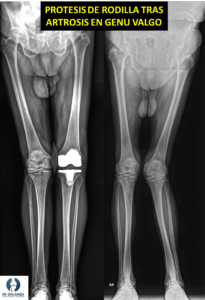

En casos de deformidad en personas mayores que padecen ya una artrosis establecida, el tratamiento puede ser implantar una prótesis de rodilla directamente, con la que podemos corregir la deformidad o parte de ella y aliviar los síntomas.

Pinche aquí para saber más sobre prótesis de rodilla